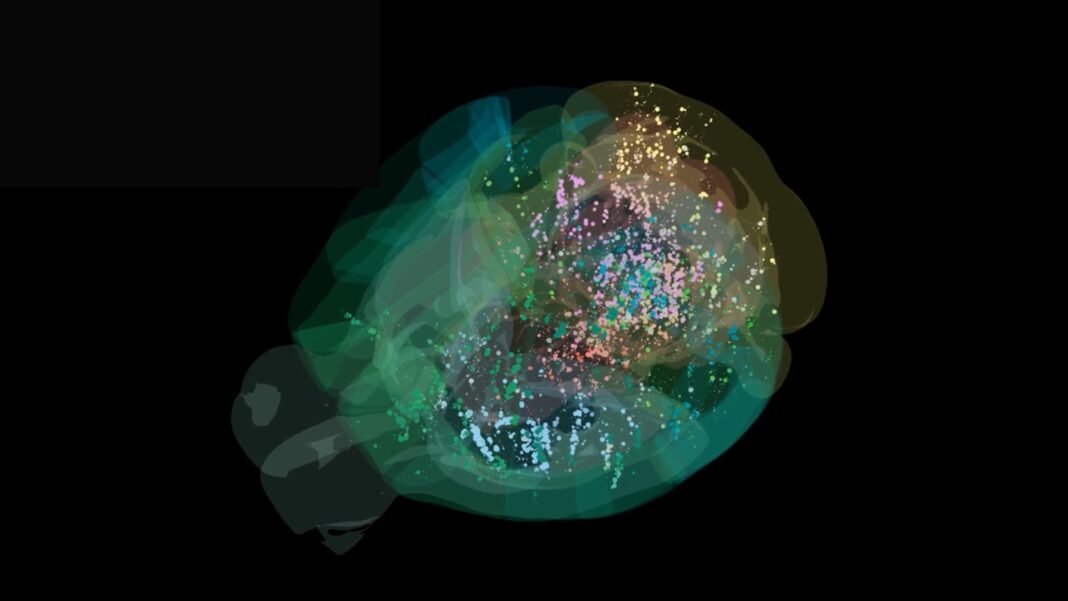

A research group in Sweden has pioneered innovative 3D bioprinting techniques aimed at fabricating thick, living skin tissues embedded with functional vascular networks crucial for tissue survival. Their approach involves two complementary strategies: one densely incorporates cells within a bio-ink matrix,while the other creates complex vascular channels inside artificial tissue using hydrogel filaments designed to mimic natural blood vessels.

The team engineered a novel bio-ink called “μInk,” which integrates fibroblasts-cells responsible for producing collagen and elastin-cultured on microscopic gelatin beads suspended within a hyaluronic acid gel base. This formulation enables precise layering through 3D printing, resulting in thick tissues densely populated with viable cells.

In experimental grafts implanted into mice, these printed constructs exhibited active cellular proliferation alongside secretion of collagen fibers that reconstructed dermal architecture. Crucially, new capillaries formed within these grafts, demonstrating their ability to support long-term integration by facilitating nutrient and oxygen delivery deep inside the tissue.

The REFRESH (Rerouting of Free-Floating Suspended Hydrogel Filaments) technique was developed as an innovative solution to build customizable vascular networks within engineered tissues. This process prints hydrogel threads composed predominantly of water (approximately 98%) but endowed with remarkable mechanical resilience-they can be knotted or braided without deformation due to their shape-memory characteristics.

A distinctive advantage of these hydrogel filaments is their enzymatic removability after embedding into tissue constructs; once dissolved cleanly without residue, they leave behind hollow microchannels resembling natural vasculature pathways. When combined with μink-based dense cell matrices during printing,this approach establishes perfusable networks capable of delivering oxygen uniformly throughout thick layers of artificial skin.